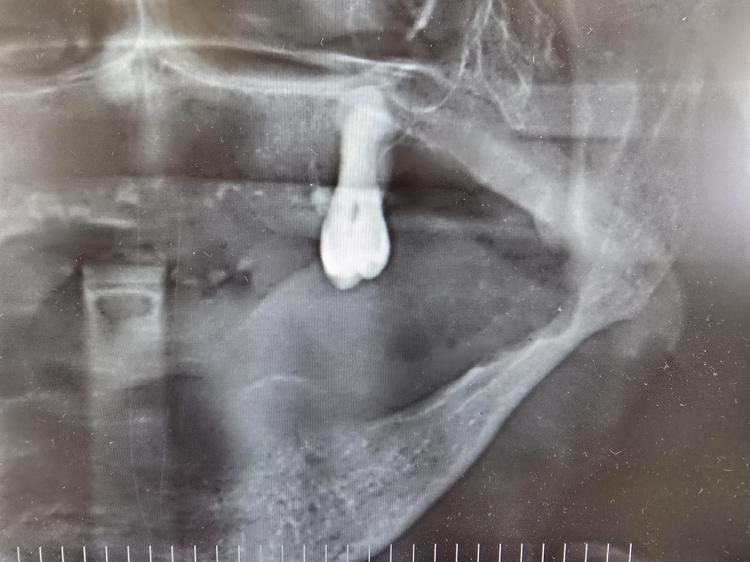

Ağız kanserinde erken tanı gerçekleşirse hastaların ölümle sonuçlanmasının önüne geçilebileceğini ifade eden Prof. Dr. Gündüz, “Biz kurum olarak Karadeniz'in en büyük üniversitesiyiz ve de fakülte olarak da Karadeniz'de büyük bir hizmet vermekteyiz. Ortalama yaklaşık günde 500 hasta, aylıkta 10 bine yakın hasta bakıyoruz. Biz yapmış olduğumuz seminerlerde hem öğrencilerimizi hem asistanlarımızı hem de halkımızı bu konuda bilgilendirmeye çalışıyoruz. Erken tanı eğer gerçekleşirse bu hastalıkların ölümle sonuçlanmasının nispeten önüne geçmiş oluyoruz. Çünkü erken tanı biliyorsunuz her kanser vakasında çok önemli bir yer tutmakta. Herhangi birisi ağzında eğer 2 haftanın üzerine geçmeyen bir yara varsa mutlaka en yakın diş hekimine başvurması gerekmekte. Sebepsiz yere dişlerin sallanması, uyuşukluk olması, yüzde sebepsiz ağrıların, çene bölgesinde sebepsiz ağrıların oluşması kanserlerin başlangıç bulguları arasındadır. Zaten kanserlerin en fazla oluştuğu yerler ağız içerisinde dilin özellikle arka kenarlarıdır. Bunlar ne yazık ki başlangıçları da ağrısız olduğu için bir kısmının gözden kaçabilmekte. O yüzden insanlarımızdan, halkımızdan bu konuda dikkat etmeleri, eğer böyle bir lezyonla muhatap olurlarsa mesela bir yakınından ağız içerisindeki görüntüsünü çekmesini talep etmeli. 2 hafta sonra da aynı şekilde bu görüntü duruyorsa veya daha da büyümüşse en yakın merkeze gitmesini önermekteyiz” ifadelerini kullandı.